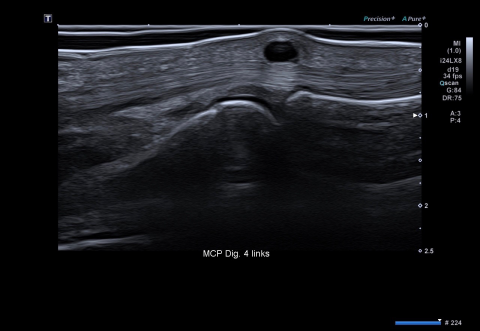

Die Intelligent-Dynamic-Microslice-Technik (iDMS) in Kombination mit den Active-Matrix-Array-Schallsonden erzeugt sehr scharf fokussierte Darstellungen mit hoher räumlicher Auflösung. Das ist besonders im Gelenkbereich sehr wichtig, um das Ausmaß von Gelenk-, Gelenkkapsel- und Sehnenentzündungen genau beurteilen zu können. Auch bei der Diagnostik von rheumatisch bedingten Gefäßentzündungen der Temporalarterien ist eine hohe Ortsauflösung extrem wichtig. Bei einem Gefäßdurchmesser von nur wenigen Millimetern beträgt die Intima-Media-Dicke dieser Gefäße nur maximal 0,4 mm. Priv.-Doz. Dr. Wolfgang Hartung vom Asklepios Klinikum Bad Abbach, Klinik und Poliklinik für Rheumatologie, Klinische Immunologie, erklärt: „Hier ist die exzellente Auflösung von großem Vorteil und erleichtert die Diagnostik früher entzündlicher Veränderungen, wodurch in der Hand eines erfahrenen Untersuchers auf eine Biopsie regelhaft verzichtet werden kann. Die frühzeitige Diagnose der Entzündung dieser Gefäße ist obligat, um die gefürchtete Komplikation einer Erblindung zu verhindern.“

Canon hat einen Doppler-Algorithmus entwickelt, der die mikrovaskuläre Versorgung einer Region sehr spezifisch darstellen kann. Dieses Superb Micro-Vascular Imaging (SMI) zur kontrastmittelfreien Untersuchung von Mikrogefäßen bietet Einblicke, die ansonsten schwer oder gar nicht möglich sind. Entzündliche Gelenkveränderungen wie z. B. eine „Synovialitis“ lassen sich mit dem Sonografiegerät von Canon Medical perfekt darstellen. Durch die Quantifizierung der synovialen Durchblutung können entzündliche Gelenkveränderungen diagnostiziert und die Aktivität der Erkrankung eingeschätzt werden. Das Ansprechen von Medikamenten, wie sie beispielsweise bei der Rheumathoiden Arthritis verabreicht werden, kann so überwacht werden und ggf. eine Dosisanpassung erfolgen. Spezifische Veränderungen der Knorpeloberfläche erlauben zusätzliche Rückschlüsse auf begleitende Kristallablagerungserkrankungen wie z. B. die Gicht oder Pseudogicht. „Durch die Anwendung der hochauflösenden Sonografie in der klinischen Routine ist die MRT für die Frühdiagnose der Rheumatoiden Arthritis, der häufigsten entzündlich rheumatischen Gelenkerkrankung, so gut wie immer entbehrlich“, legt Dr. Hartung dar.